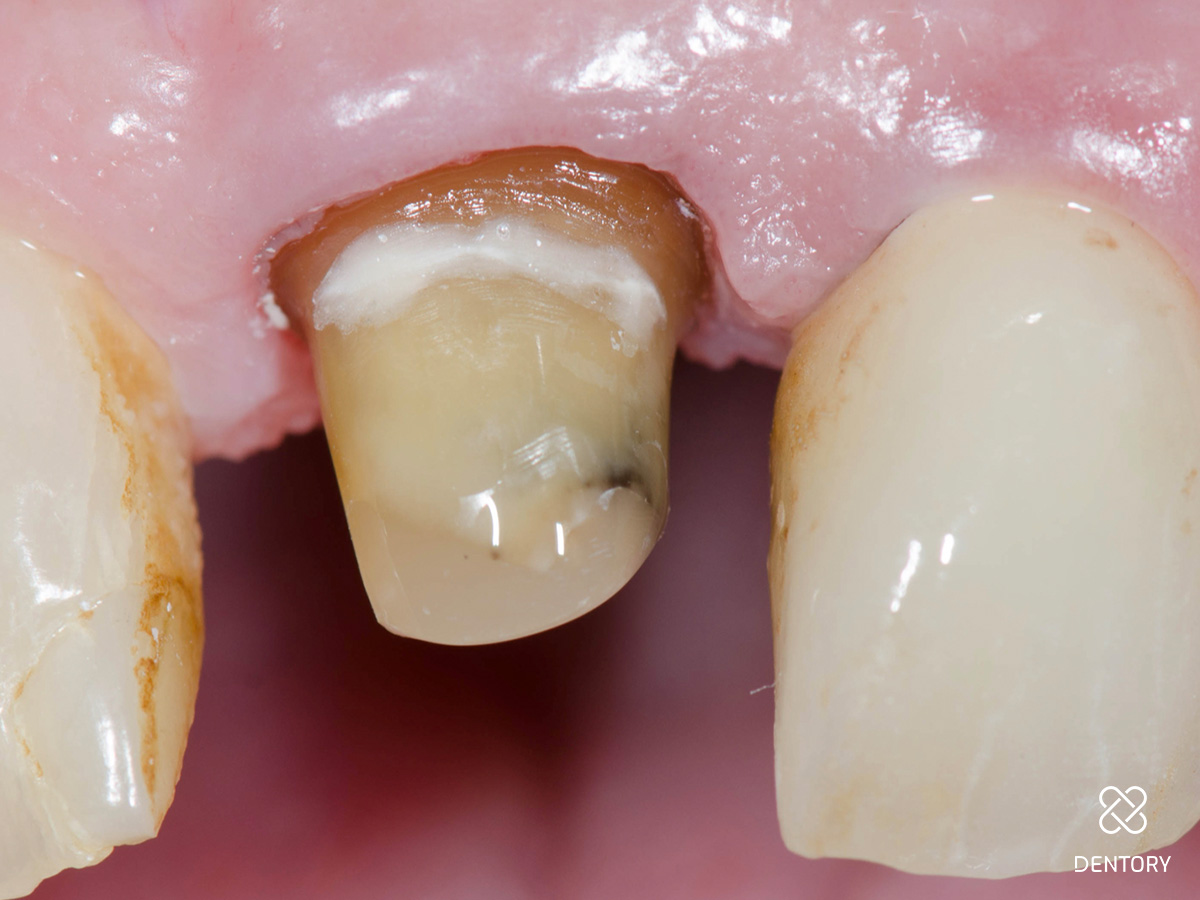

Abbildung 3

Kronenentfernung: Die Zähne waren wurzelkanalbehandelt und mit einem Stift versorgt. Das Bild zeigt die Situation nach Abnahme der Krone und Präparation der Stümpfe.